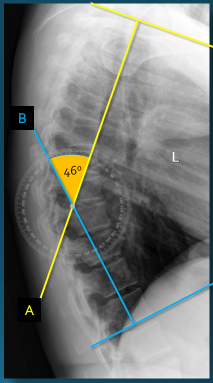

Q what is the name of this measurement? and what is the average + range?

A: Sacral Inclination

assesses the angle of the sacrum relative to a vertical line. The average is 46°, with a range of 30-72°.